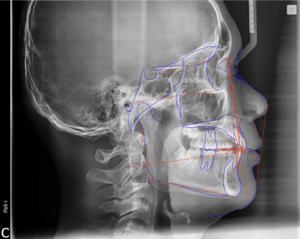

- Diagnostic X-rays

- Bite and jaw alignment analysis

- Facial profile evaluation